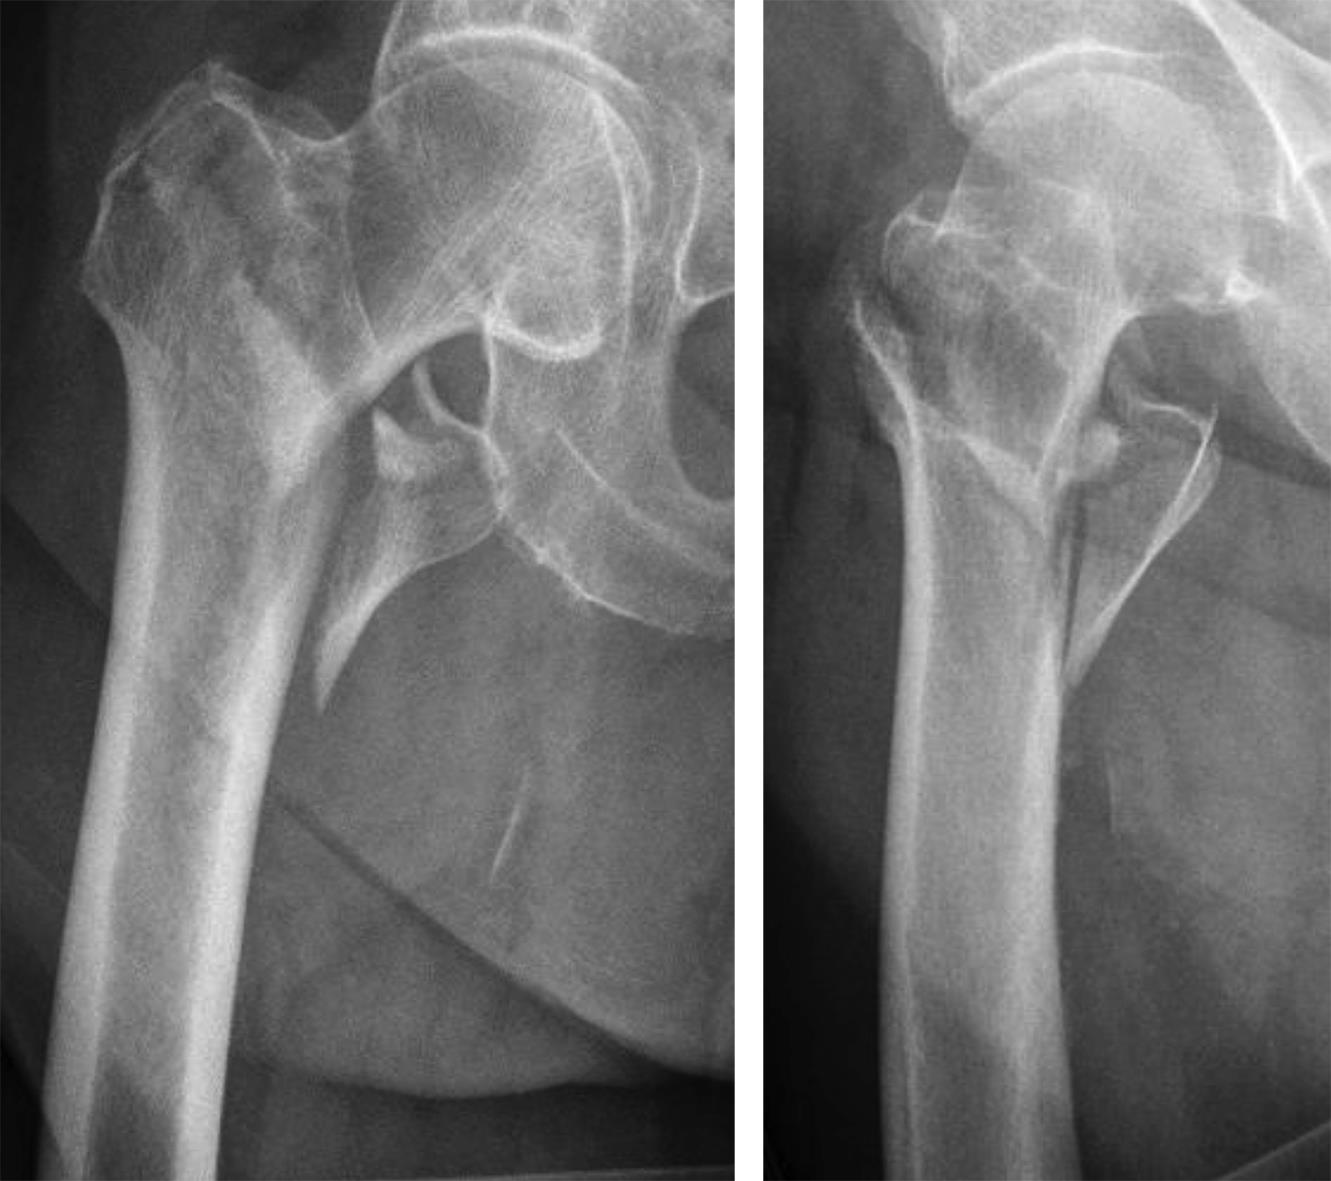

Features to avoid loss of closed reduction during nail insertion

Surgeons often report some loss of reduction during nail insertion, specifically in cases involving nail insertion through a fractured greater trochanter. This often leads to an unintended varisation of the head-neck fragment (HNF) and a medialization of the HNF resulting in reduced bone contact in the calcar area (Fig 2 and 3).

The combination of a large proximal nail diameter and a very lateral entry point has been identified as a potential reason for such a loss of reduction. As a result, a smaller diameter nail with a laterally flattened profile to more appropriately respect the anatomy of the proximal lateral femoral wall would be advantageous. Both design features have been realized with the new nail. The smaller 15.66 mm proximal nail diameter of the TFNA (compared to 16.5 mm and 17 mm for PFNA/PFNA-II and TFN) and the LATERAL RELIEF CUT design (Fig 4) of the proximal nail end serve to reduce the potential impingement of the nail with the lateral femoral wall and the HNF. Both of these issues could result in varus malalignment and a loss of reduction, which remain key indicators for an increased risk of cut-out. The small proximal nail diameter also helps to preserve bone in the insertion area, which is especially beneficial in the femora of small stature patients.